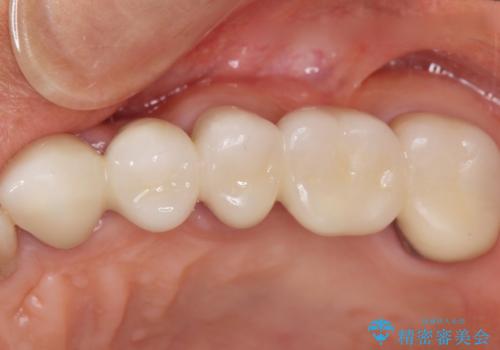

自然な仕上がりと咬み心地に喜んで下さいました。

歯茎の腫れも治り、ご満足頂けました。

クラウンの種類:メタルボンドクラウン エコノミー